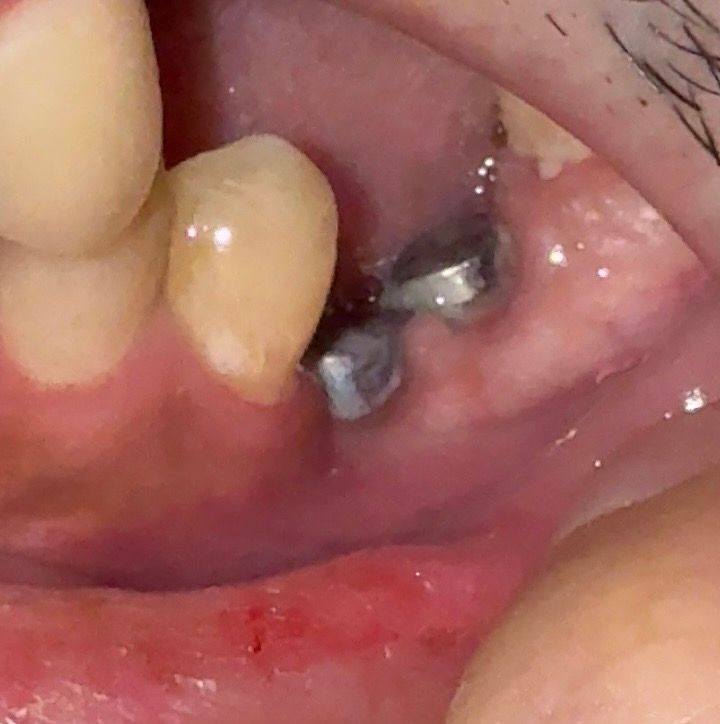

사진에서 보시면 아래쪽 잇몸이 많이 꺼져있는것 같은데 보철물 부착을 할 수 있는지 궁금합니다

• 1번 째 사진